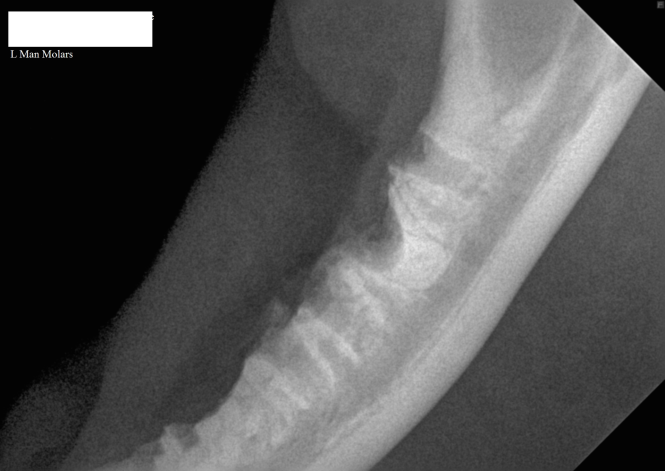

3. Intra-oral radiograph of the left mandible of a cat with a retained mesial root of the molar tooth